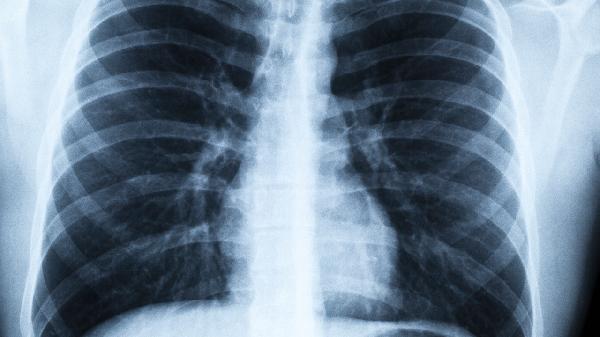

34岁女子肺结节,在上海做了微创手术,术后感觉比想象中要严重

34岁就查出肺结节,这个年纪确实让人心头一紧。那位在上海做完微创手术的女士,术后反应比预期强烈的情况,其实不少人都经历过。肺结节手术虽说是“微创”,但毕竟是在重要器官上操作,术后反应因人而异很正常。